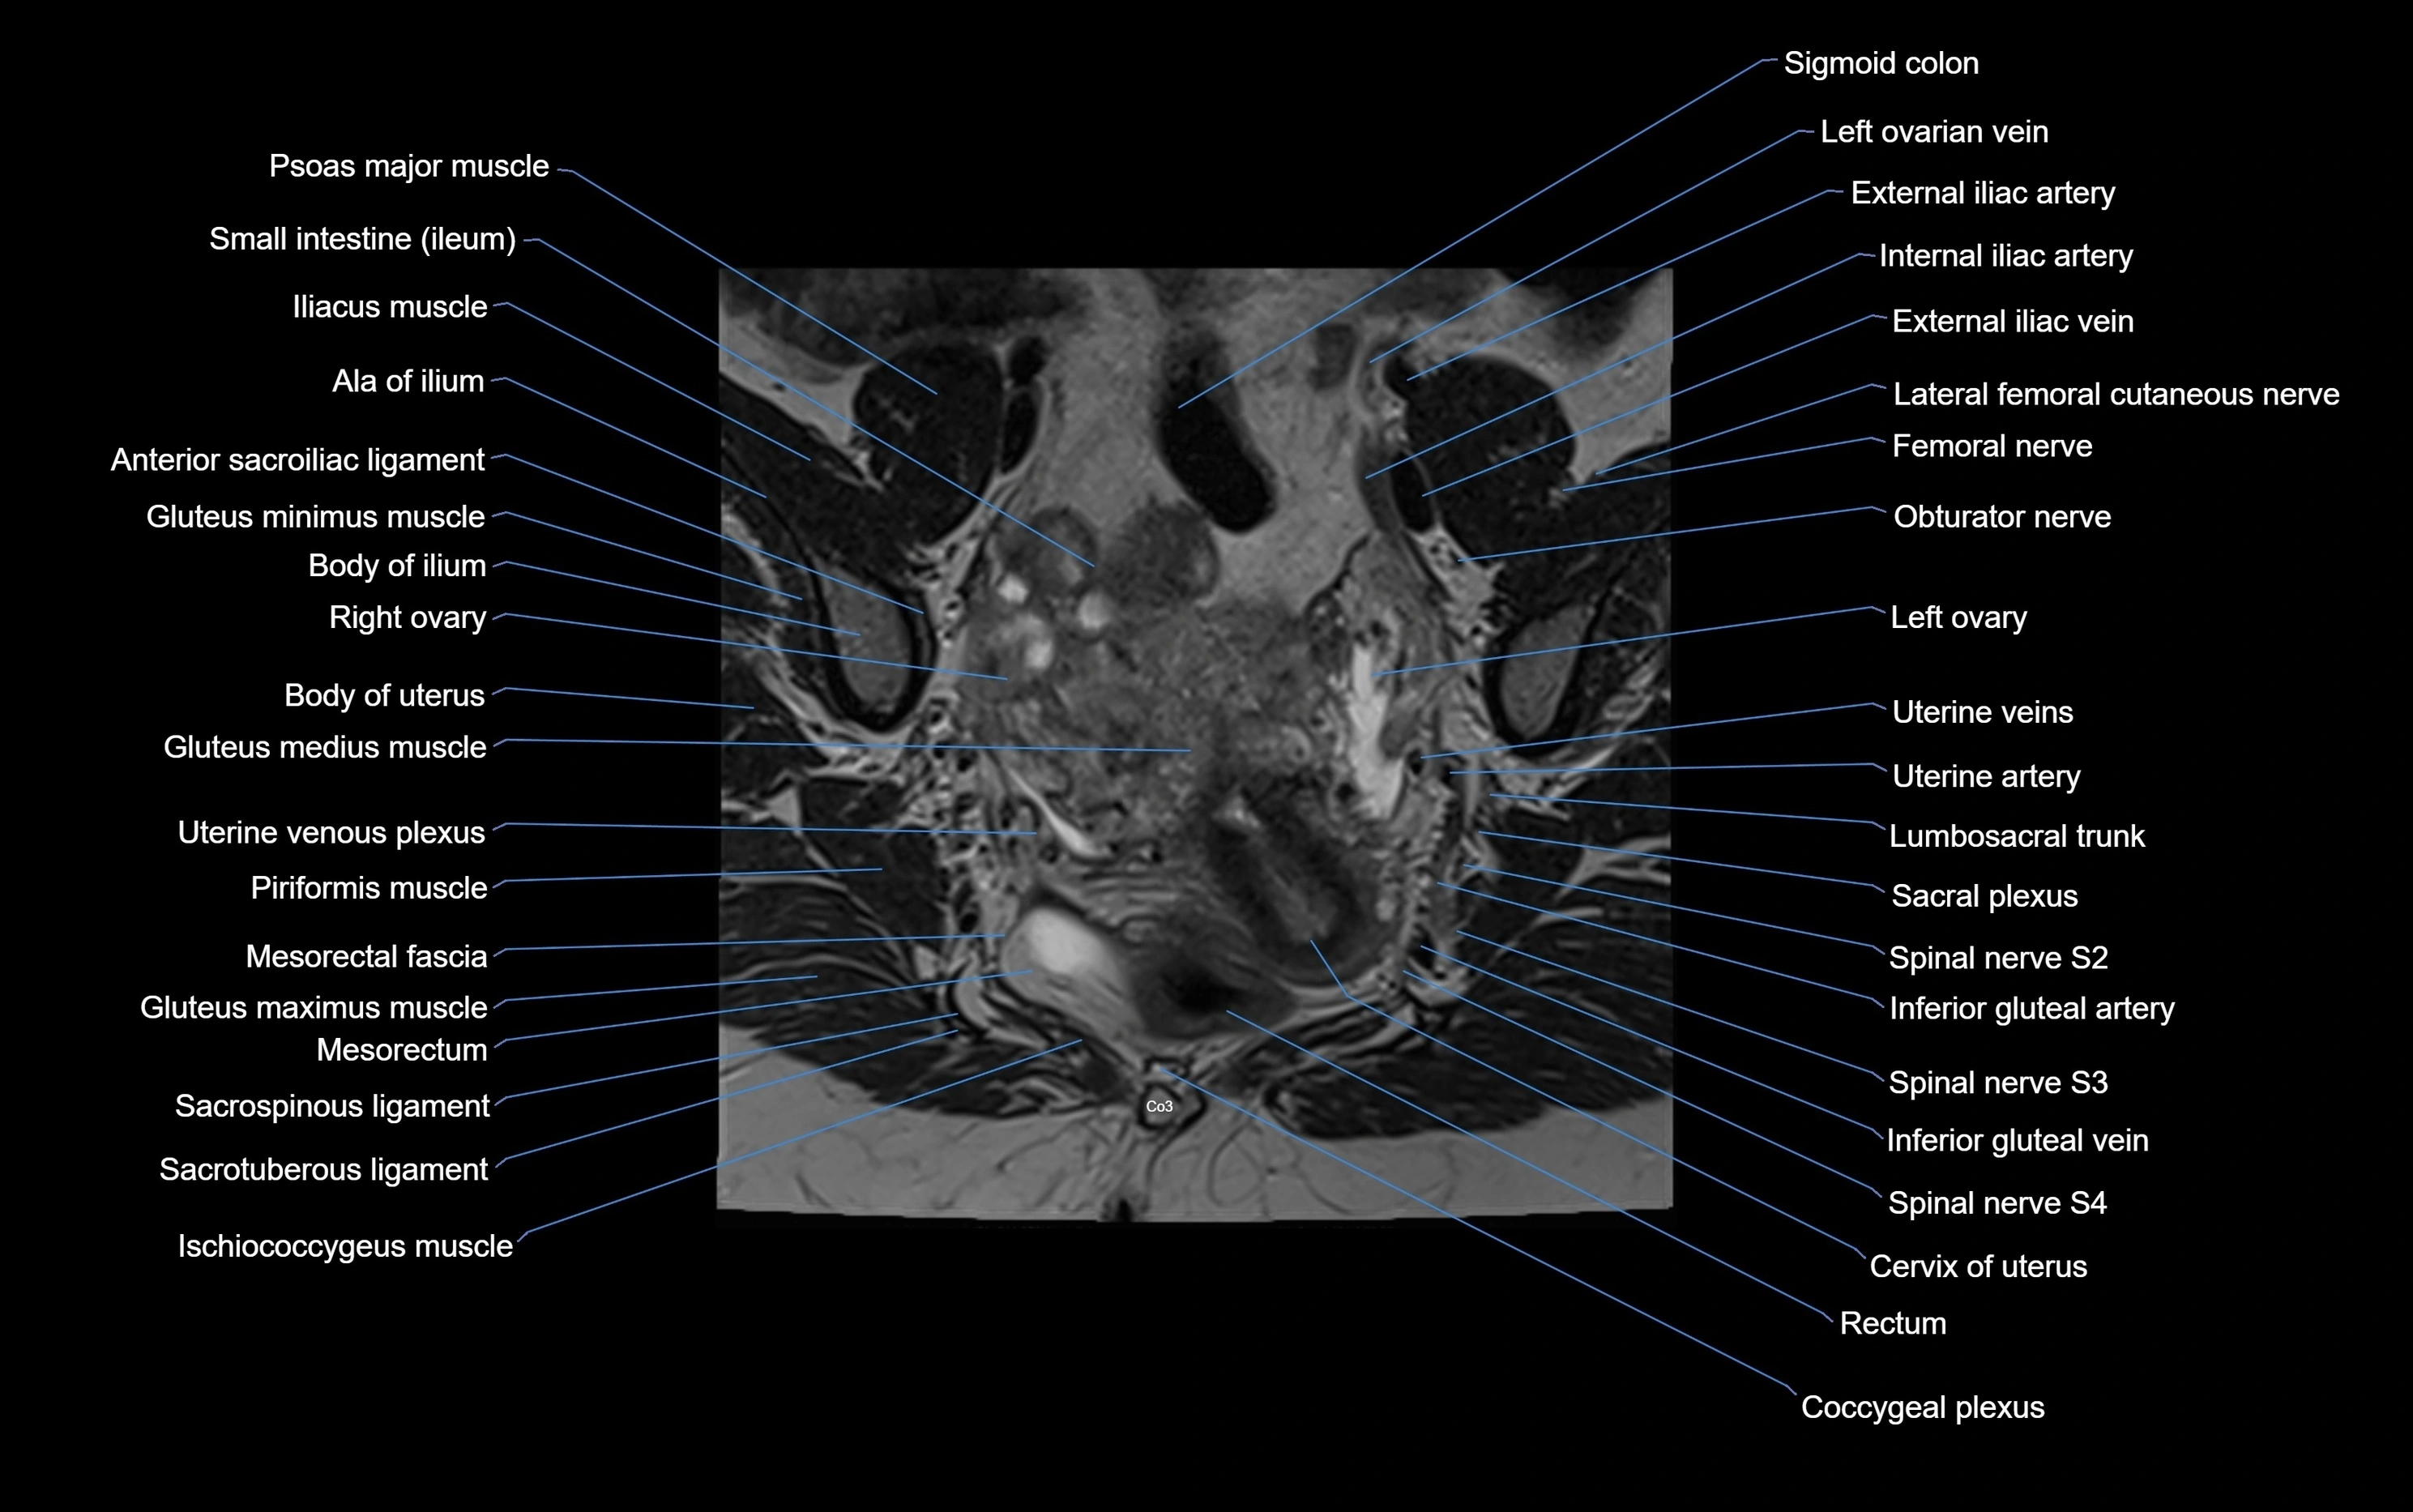

MRI image

image